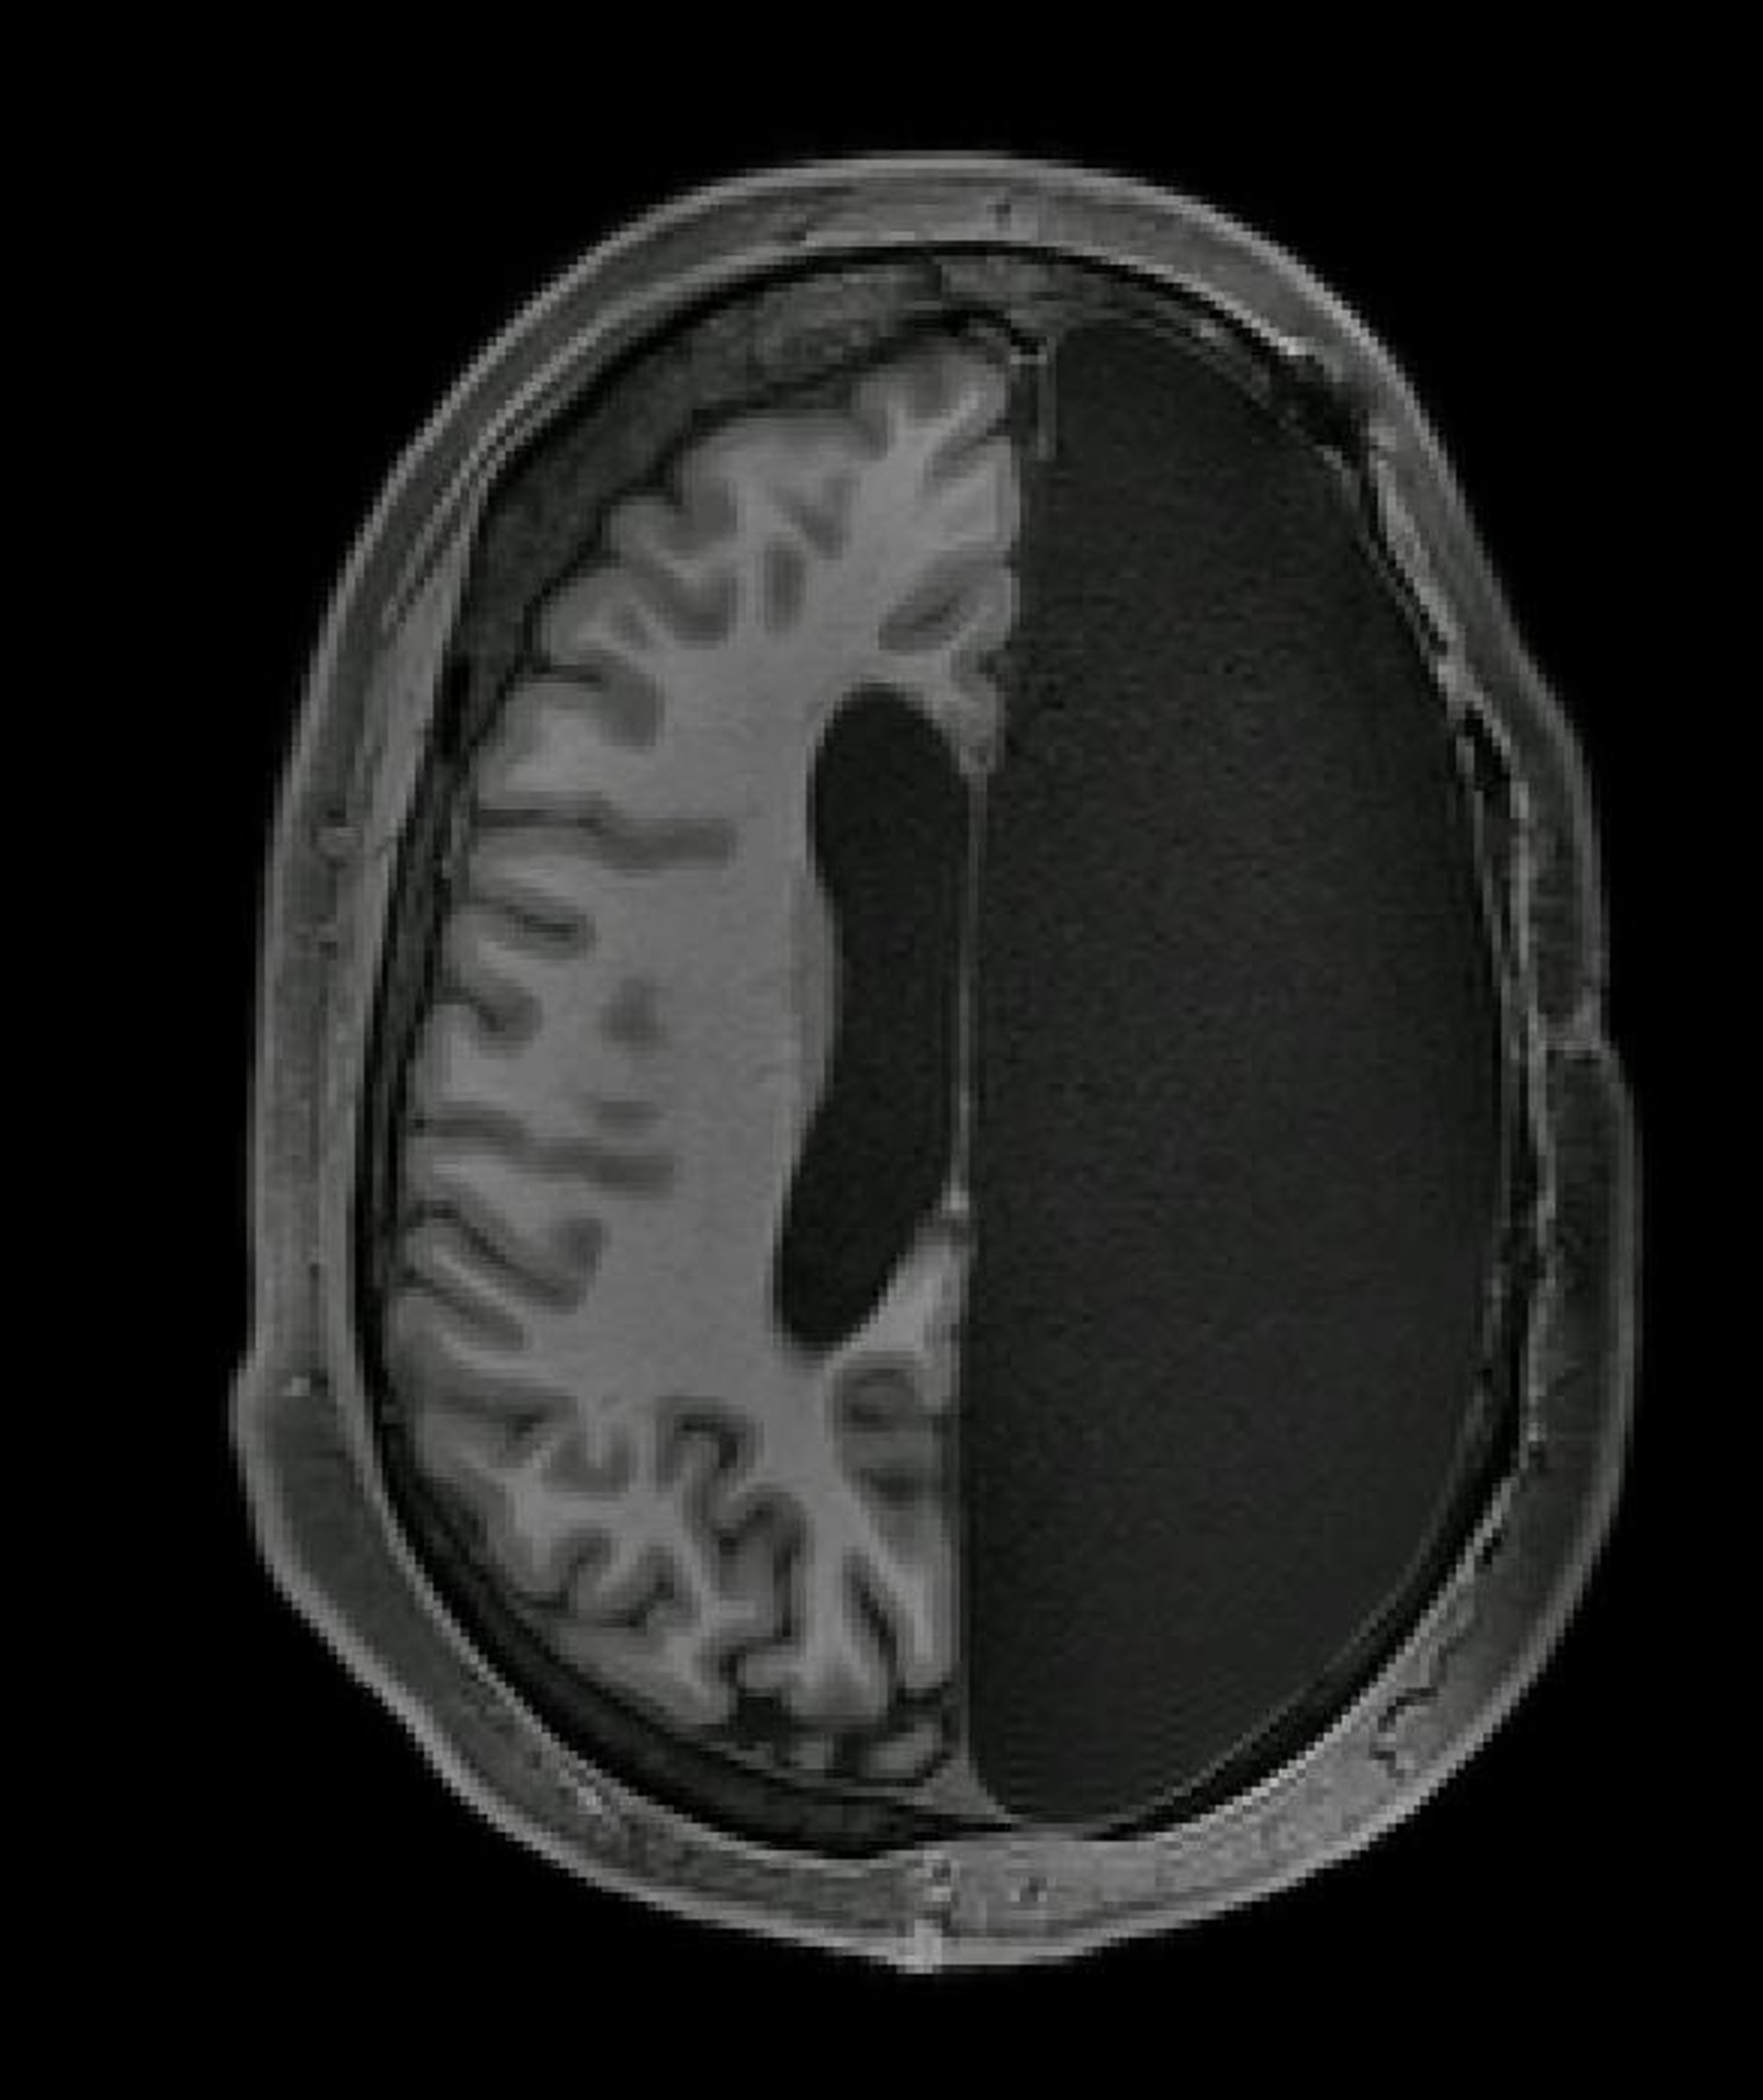

Imagen fr resonancia magnéticaque muestra el cerebro de un adulto al que se le extirpó un hemisferio completo durante la infancia debido a la epilepsia. Hemisferectomía.

Imagen fr resonancia magnéticaque muestra el cerebro de un adulto al que se le extirpó un hemisferio completo durante la infancia debido a la epilepsia. Hemisferectomía. - CALTECH BRAIN IMAGING CENTER

"Casi puedes olvidar su condición cuando los conoces por primera vez --asegura--. Cuando me siento frente a la computadora y veo sus imágenes de resonancia magnética que muestran solo medio cerebro, todavía me maravillo de que las imágenes provengan del mismo ser humano que yo acabo de ver hablar y caminar y quién eligió dedicar su tiempo a la investigación".